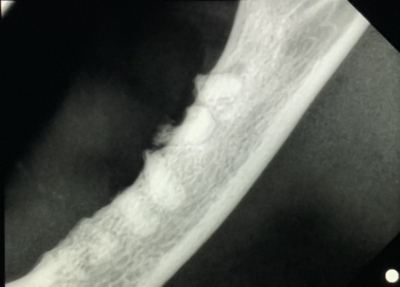

歯科レントゲンで下顎の画像。数本並んでいる白いのが折れて残っている歯根。これを残すと治らない。